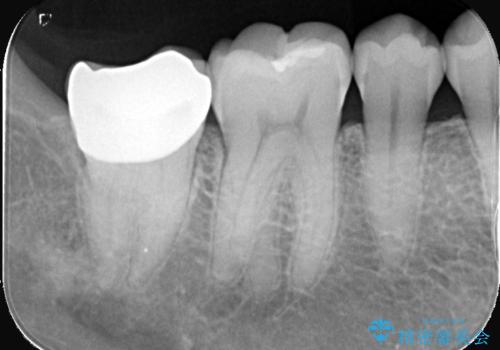

- 頬側に大きな虫歯があり、神経に達している可能性が高かったため、虫歯除去時に神経が出た場合はVPTを提案しました。

虫歯が神経まで達していましたが、術前の検査でVPTの適応と診断をしていたので、ラバーダムシートを装着しVPTを行いました。

経過も良好で、痛みも無く神経を残すことが出来ました。